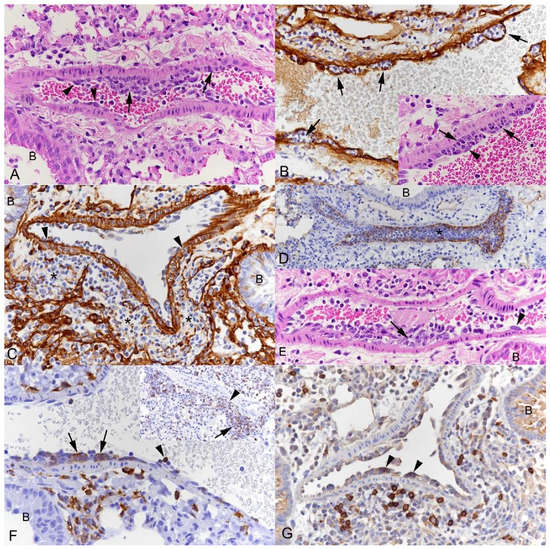

3.1. Pulmonary Vasculitis Is a Consistent Feature of SARS-CoV-2 Infection in Mouse Models

3.2. Respiratory Virus Infections, with Variable Degree of Alveolar Damage, and with or without Damage to Respiratory Epithelium, Elicit a Stereotypic Vascular Response

3.4. The Vascular Response after Respiratory Virus Infections Is Associated with Increased Expression of Adhesion Molecules in the Lungs